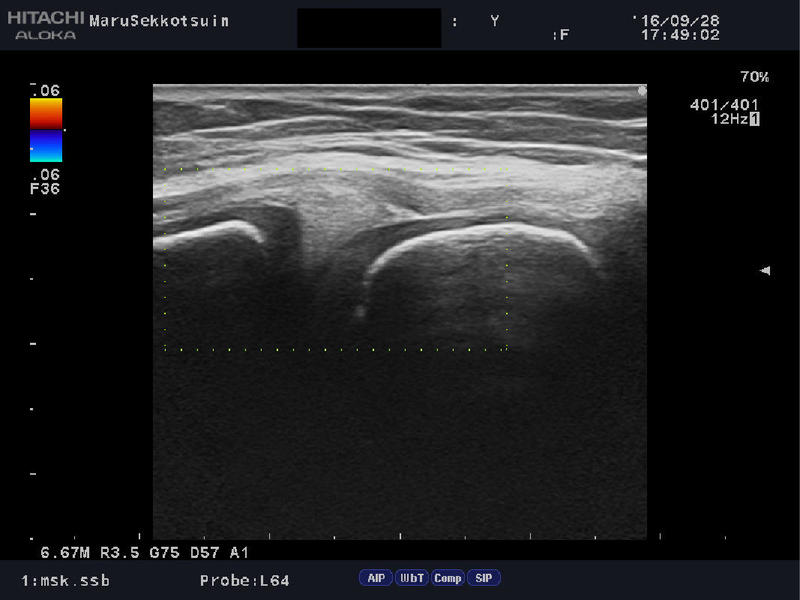

しっかり問診し、触診、エコー検査にて、

「膝内側側副靭帯損傷」と判明。

mcl echo.jpg

今回は腫脹、圧痛は診られるものの、側方への動揺性は診られませんでした。